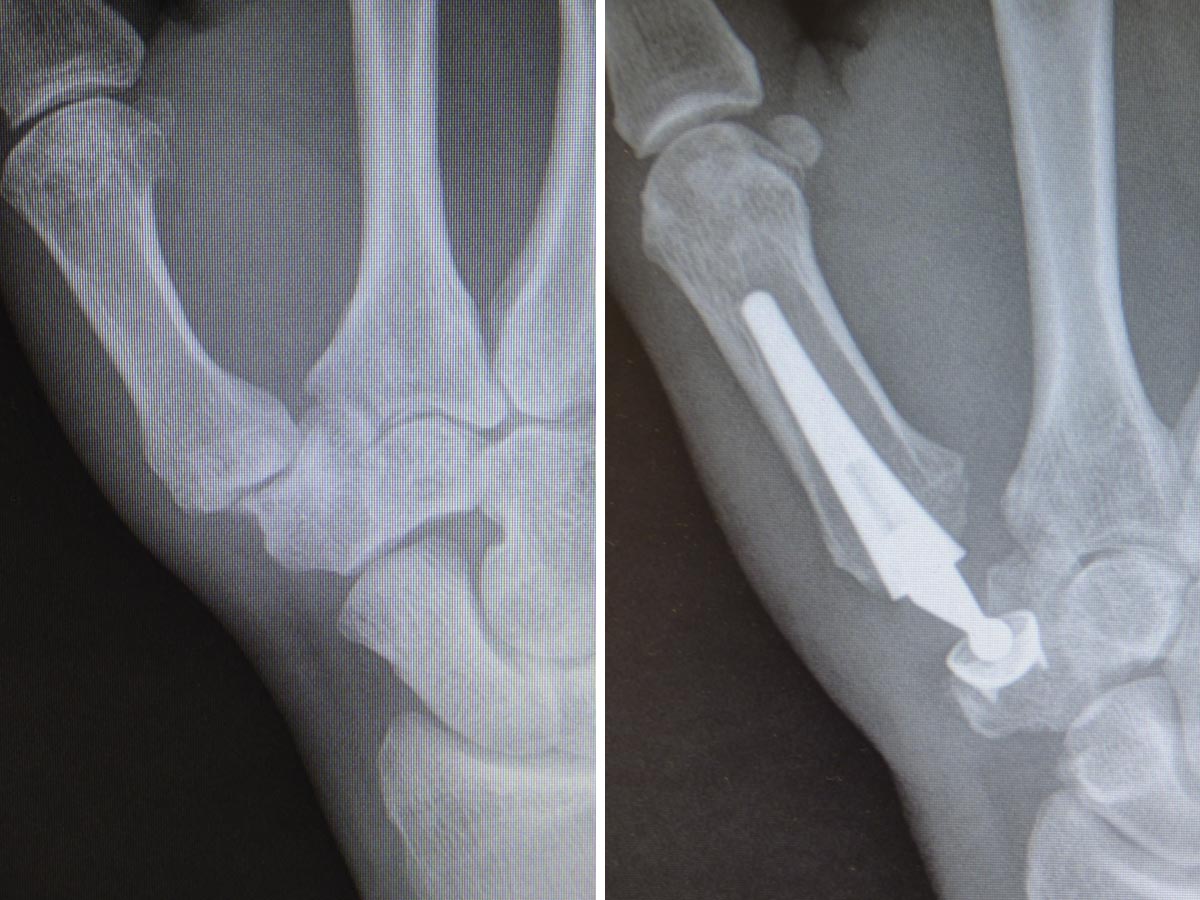

RIZARTROSIS (artrosis en la base del pulgar)

La rizartrosis es el cambio degenerativo de la articulación trapecio-metacarpiana (TMC), constituye una enfermedad muy habitual, especialmente en mujeres mayores de 50 años. Cerca del 30% de las mujeres posmenopáusicas presentan cambios degenerativos radiográficos en la articulación TMC, aunque algunas son asintomáticas . Menos frecuentemente esta enfermedad afecta a los hombres (menos del 10%).

Es una patología muy incapacitante, ya que produce dolor a la movilización del pulgar, disminución de la fuerza, perdida de destreza en la pinza, limitación de la movilidad y deformidad progresiva de la columna del pulgar por aducción del 1er dedo, subluxación radial de la base del 1er metacarpiano y la consiguiente hiperextensión de la articulación metacarpofalangica.

La clasificación de Eaton y Littler esta destinada a hacer una elección terapéutica racional entre los diferentes métodos en función de los estadios evolutivos radiológicos.

Las artroplastias TMC también se han empleado para esta patología. Existen numerosos modelos. El implante ideal debe permitir una reconstrucción articular anatómica, debe ser biocompatible, con un periodo de supervivencia largo, no cementado para evitar los problemas frecuentes de descementación o aflojamiento en la interfase cemento-hueso y no debería constituir la última solución terapéutica posible en caso de fracaso